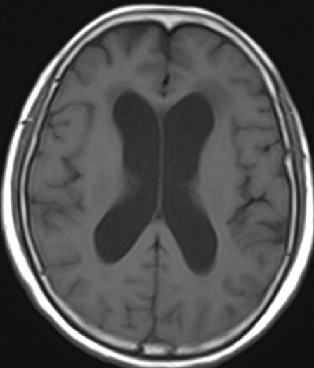

2014-10-17 CT

仍时有前额部疼痛,程度轻,调压190—200